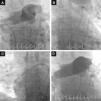

Two of our patients were referred due to contraindication to thrombolysis and the other for failure of thrombolysis to improve hemodynamics. At the time of the procedure two patients were sedated and ventilated, and all were under inotropic support. The right femoral vein was punctured and a 7F introducer was inserted, followed by arteriography of the pulmonary artery trunk and selective arteriography of the right and left pulmonary arteries using a 6F angled pigtail catheter. A 0.035″ hydrophilic guidewire was then positioned in the affected pulmonary artery and the 6F dual-lumen AngioJet® catheter was advanced. The catheter was activated proximally to distally, with one or two complete passes. The procedure was repeated for the affected lobar arteries and for the contralateral pulmonary artery if necessary. An angiographic review was performed at the end of the procedure (Figure 4). The intervention should be halted as soon as hemodynamic recovery is confirmed or if the total activation time recommended by the manufacturer is reached, irrespective of the final angiographic result. In the last patient, it was decided to implant a temporary transvenous pacemaker by a femoral route at the beginning of the procedure. Following the procedure, all patients were transferred to the ICU.

Fluoroscopic images during initial arteriography of the pulmonary trunk (more selective for the right pulmonary artery), showing massive bilateral pulmonary embolism with thrombi in the main pulmonary arteries and involving all the lobar arteries, with significant flow obstruction (A); 6F AngioJet® catheter positioned in the left pulmonary artery (B) and in the right pulmonary artery (C); final image, demonstrating slight angiographic improvement but with immediate improvement in hemodynamics and gas exchange (D).